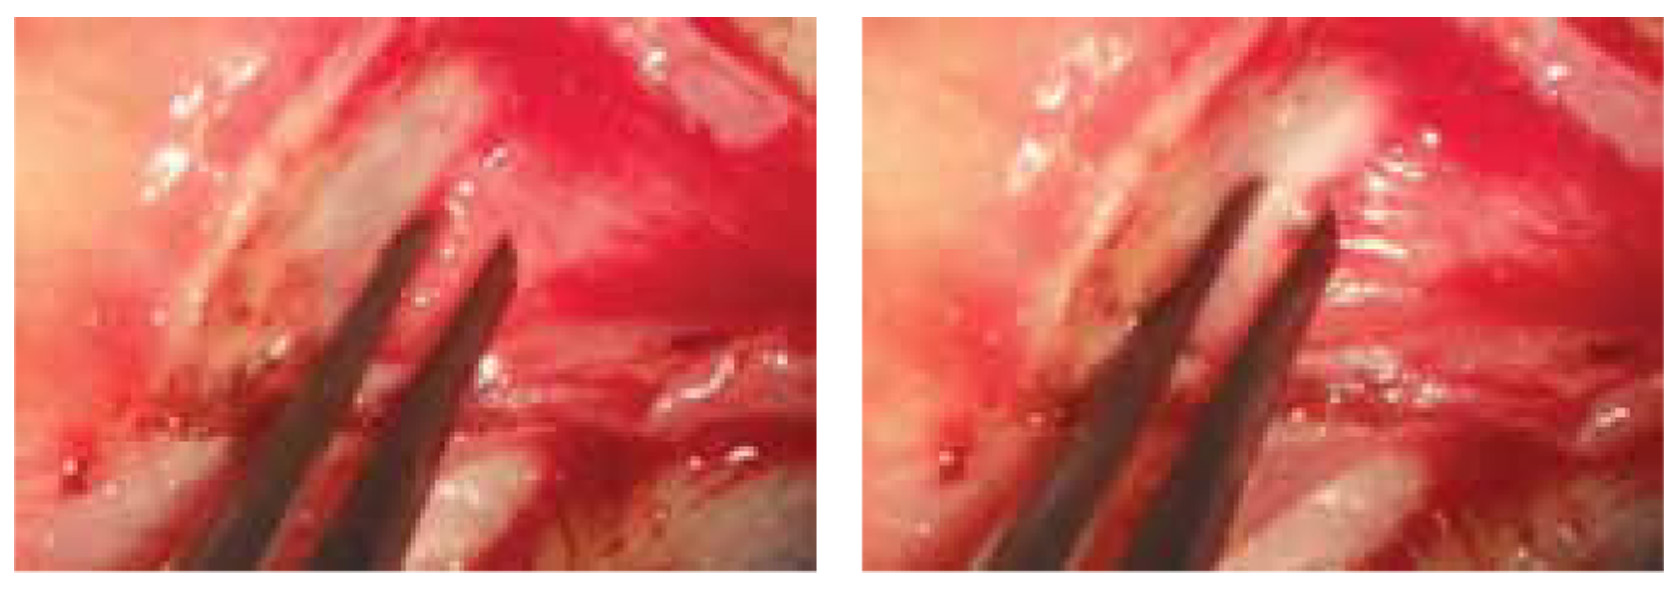

The test was performed as follows. A traction suture was placed on the edge of the upper eyelid (Vycril 4/0). The upper eyelid was turned out using a Desmarres retractor (Fig. 2, a). The conjunctiva and STM were dissected from the upper edge of the tarsal plate (Fig. 2, b). The white line was identified, and its mobility was assessed by pulling the belly of the STM (Fig. 2, c, d). The volume of STM resection and possible excision of the upper eyelid tarsal plate were then planned according to the degree of white line mobility.

Fig. 2. White line motility test

Рис. 2. Интраоперационный тест оценки подвижности белой линии (описание в тексте)